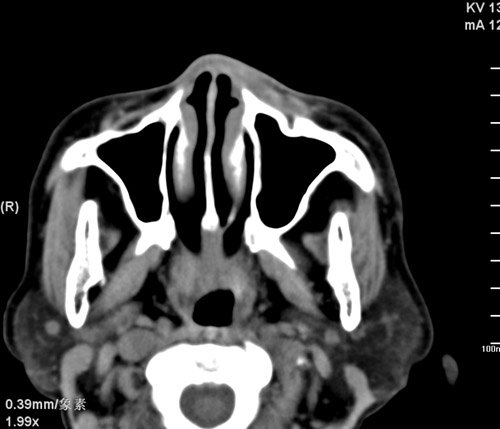

标题: CT17755:女,74 左鼻旁肿胀半年,临床以左上颌窦旁占位行CT [打印本页]

标题: CT17755:女,74 左鼻旁肿胀半年,临床以左上颌窦旁占位行CT

ct考虑鼻前庭囊肿 或鼻翼基底部慢性炎症,左上颌窦少许炎症 请指教

1)考虑左侧鼻前庭囊肿并感染。2)双侧上颌窦炎。

左侧鼻前庭囊肿并感染。双侧上颌窦炎。支持